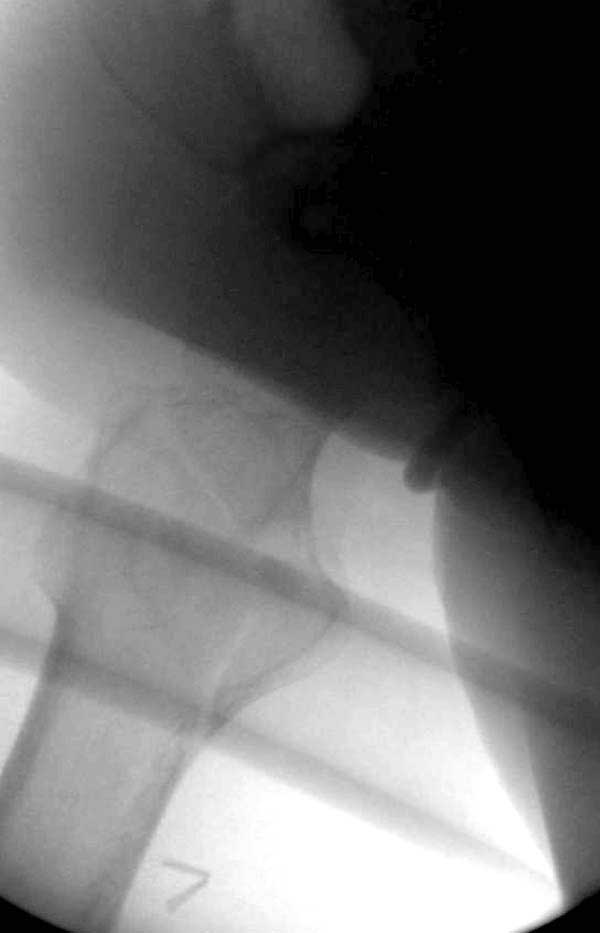

Вторая операция- это фаза сохранения головки бедра. Желательно приложить все усилия и сохранить головку, но, как видно, “фиаско” продолжается. Здесь вместо нейтрализации сил между медиальной и латеральными сторонами была попытка удержать варус. Варус не удержать ни деротационными шурупами о котором говорили и не костными стружками вбитые в шейку, потому что вся нагрузка упирается в головку.

Как отметил Евгений, 95 degree Blade Plate Fixed Angle device  расчитана на восстановление взаимоотношении между головкой и диафизом, а все остальные фиксаторы (Gamma, Afifuxus и др.) работают за счет нагрузки в верхнем полюсе головки. Верхний полюс успели разрушить, и в головке единственное место, который смог бы удержать широкий клинок конструкции, это медиально-низкий сегмент. После установки клинка засчет дистракции можно удлинить конечность на 15мм, а добавленный в дефект ауто-графт закончил бы дело.